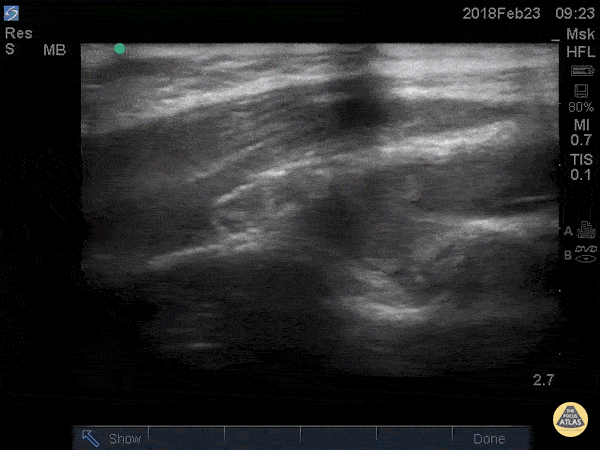

Musculoskeletal - Posterior Fat Pad

Posterior fat pad aka Sail sign, is one of the common findings that we look for after a traumatic elbow injury that can indicate an underlying fracture. It represents hemarthrosis pushing the fat pad superiorly causing the triceps tendon to tilt. Plain films has been used as the initial modality of choice to look for sail sign but POCUS has been shown to be highly sensitive (97%) and specific (88%). It can be seen as anechoic fluid between the olecranon, humerus and fat pad. Source: Avci et. al. (PMID: 27645809). Also note the broken crystal on this image causing a dark artifact anteriorly. Dr. Maan Al Dubayan, Steven Greenstein, and Matthew Riscinti - Kings County Emergency Medicine